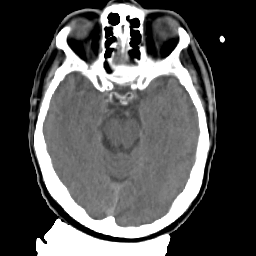

Meningioma: Roentgen-ray CT #2 -- Slice #7

[Home][Help][Clinical] Slice 7